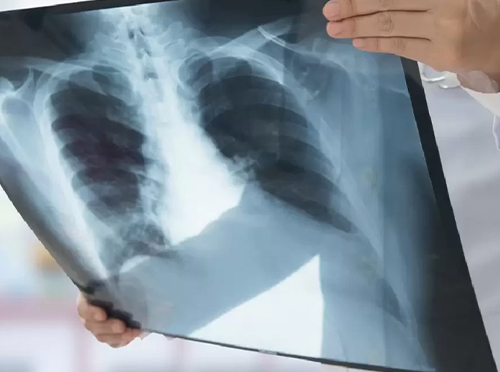

يقدم قسم الأشعة بمجمع الأحمدي الطبي خدمات تصوير طبية متقدمة تعتمد على أحدث الأجهزة والتقنيات الحديثة، مع فريق متخصص من الأطباء والفنيين لضمان تشخيص سريع ودقيق.

- الأشعة السينية (X-Ray)